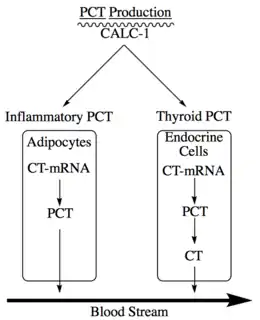

PCT is a member of the calcitonin (CT) superfamily of peptides. It is a peptide of 116 amino acids with an approximate molecular weight of 14.5 kDa, and its structure can be divided into three sections (see Figure 1):[9] amino terminus (represented by the ball and stick model in Figure 1), immature calcitonin (shown in Figure 1 from PDB as the crystal structure of procalcitonin is not yet available), and calcitonin carboxyl-terminus peptide 1.[9] Under normal physiological conditions, active CT is produced and secreted in the C-cells of the thyroid gland after proteolytic cleavage of PCT, meaning, in a healthy individual, that PCT levels in circulation are very low (<.05 ng/mL). The pathway for production of PCT under normal and inflammatory conditions are shown in Figure 2.[10] During inflammation, LPS, microbial toxin, and inflammatory mediators, such as IL-6 or TNF-α, induce the CALC-1 gene in adipocytes, but PCT never gets cleaved to produce CT.[10] In a healthy individual, PCT in endocrine cells is produced by CALC-1 by elevated calcium levels, glucocorticoids, CGRP, glucagon, or gastrin, and is cleaved to form CT, which is released to the blood.[10]

PCT is located on the CALC-1 gene on chromosome 11.[9] Bacterial infections induce a universal increase in the CALC-1 gene expression and a release of PCT (>1 μg/mL).[11] Expression of this hormone occurs in a site specific manner.[9] In healthy and non-infected individuals, transcription of PCT only occurs in neuroendocrine tissue, except for the C cells in the thyroid. The formed PCT then undergoes post-translational modifications, resulting in the production small peptides and mature CT by removal of the C-terminal glycine from the immature CT by peptidylglycine α-amidating monooxygenase (PAM).[12] In a microbial infected individual, non-neuroendocrine tissue also secretes PCT by expression of CALC-1. A microbial infection induces a substantial increase in the expression of CALC-1, leading to the production of PCT in all differentiated cell types.[13] The function of PCT synthesized in nonneuroendocrine tissue due to a microbial infection is currently unknown, but, its detection aids in the differentiation of inflammatory processes.[9]